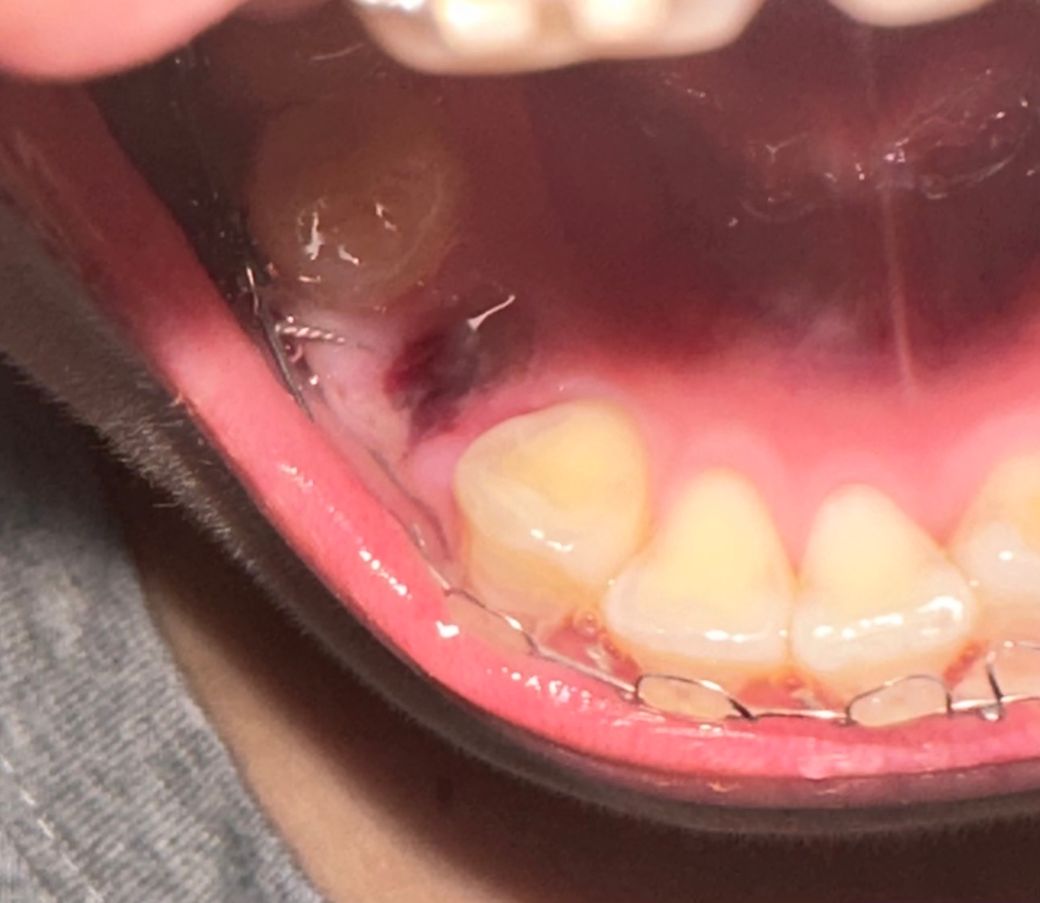

단순 어금니 작은 구치 발치 드라이소켓 의심?

제가 전자담배 흡연자인데 이틀전에 왼쪽 어금니랑 아래 작은구치 발치 했는데요 솔직히 신경 잘 안쓰고 전자담배 평소보다 조금 약하게 피웠는데 혈병이 떨어진 느낌이 나는데 어떤가요?…. 그리고 발치 부위에 따라 드라이소켓 발병률이 높나요? 궁금합니다ㅜㅜ

사진으로만 봤을 경우에는 드라이 소켓으로 보이진 않습니다 해당 부위의 혈병을 제거되지 않도록 발치된 부위를 자극하지 않는 것이 좋습니다

현재 사진에서는 발치 이후에 정상적인 회복 과정으로 보여집니다. 드라이소켓이라면 해당 부분이 농에 차 보이게 됩니다. 통증이나 특별히 불편감이 없다면 크게 걱정하지 않으셔도 됩니다. 사진 사엥서는 큰 문제가 없어 보입니다.

드라이 소켓은 아닌거 같습니다. 발치하고 지혈잘되시고 통증이 없다면 너무 걱정하지 않으셔도 됩니다.

사진상으로는 드라이소켓이 발생한것으로 보이지는 않습니다. 하지만 발치부위가 덧나는 것을 예방하기 위해서는 7일간은 음주 및 흡연은 반드시 피하길 권합니다.